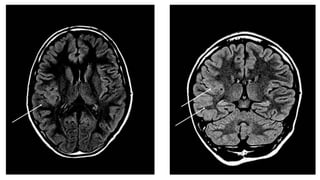

MRI brain

• Gliosis involving left paracentral

lobule, extending to left parietal

region.

• Subcortical gliosis near the

motor strip.

• Secondary left hippocampal

changes.

fMRI: hand and leg area abutting

the lesion.